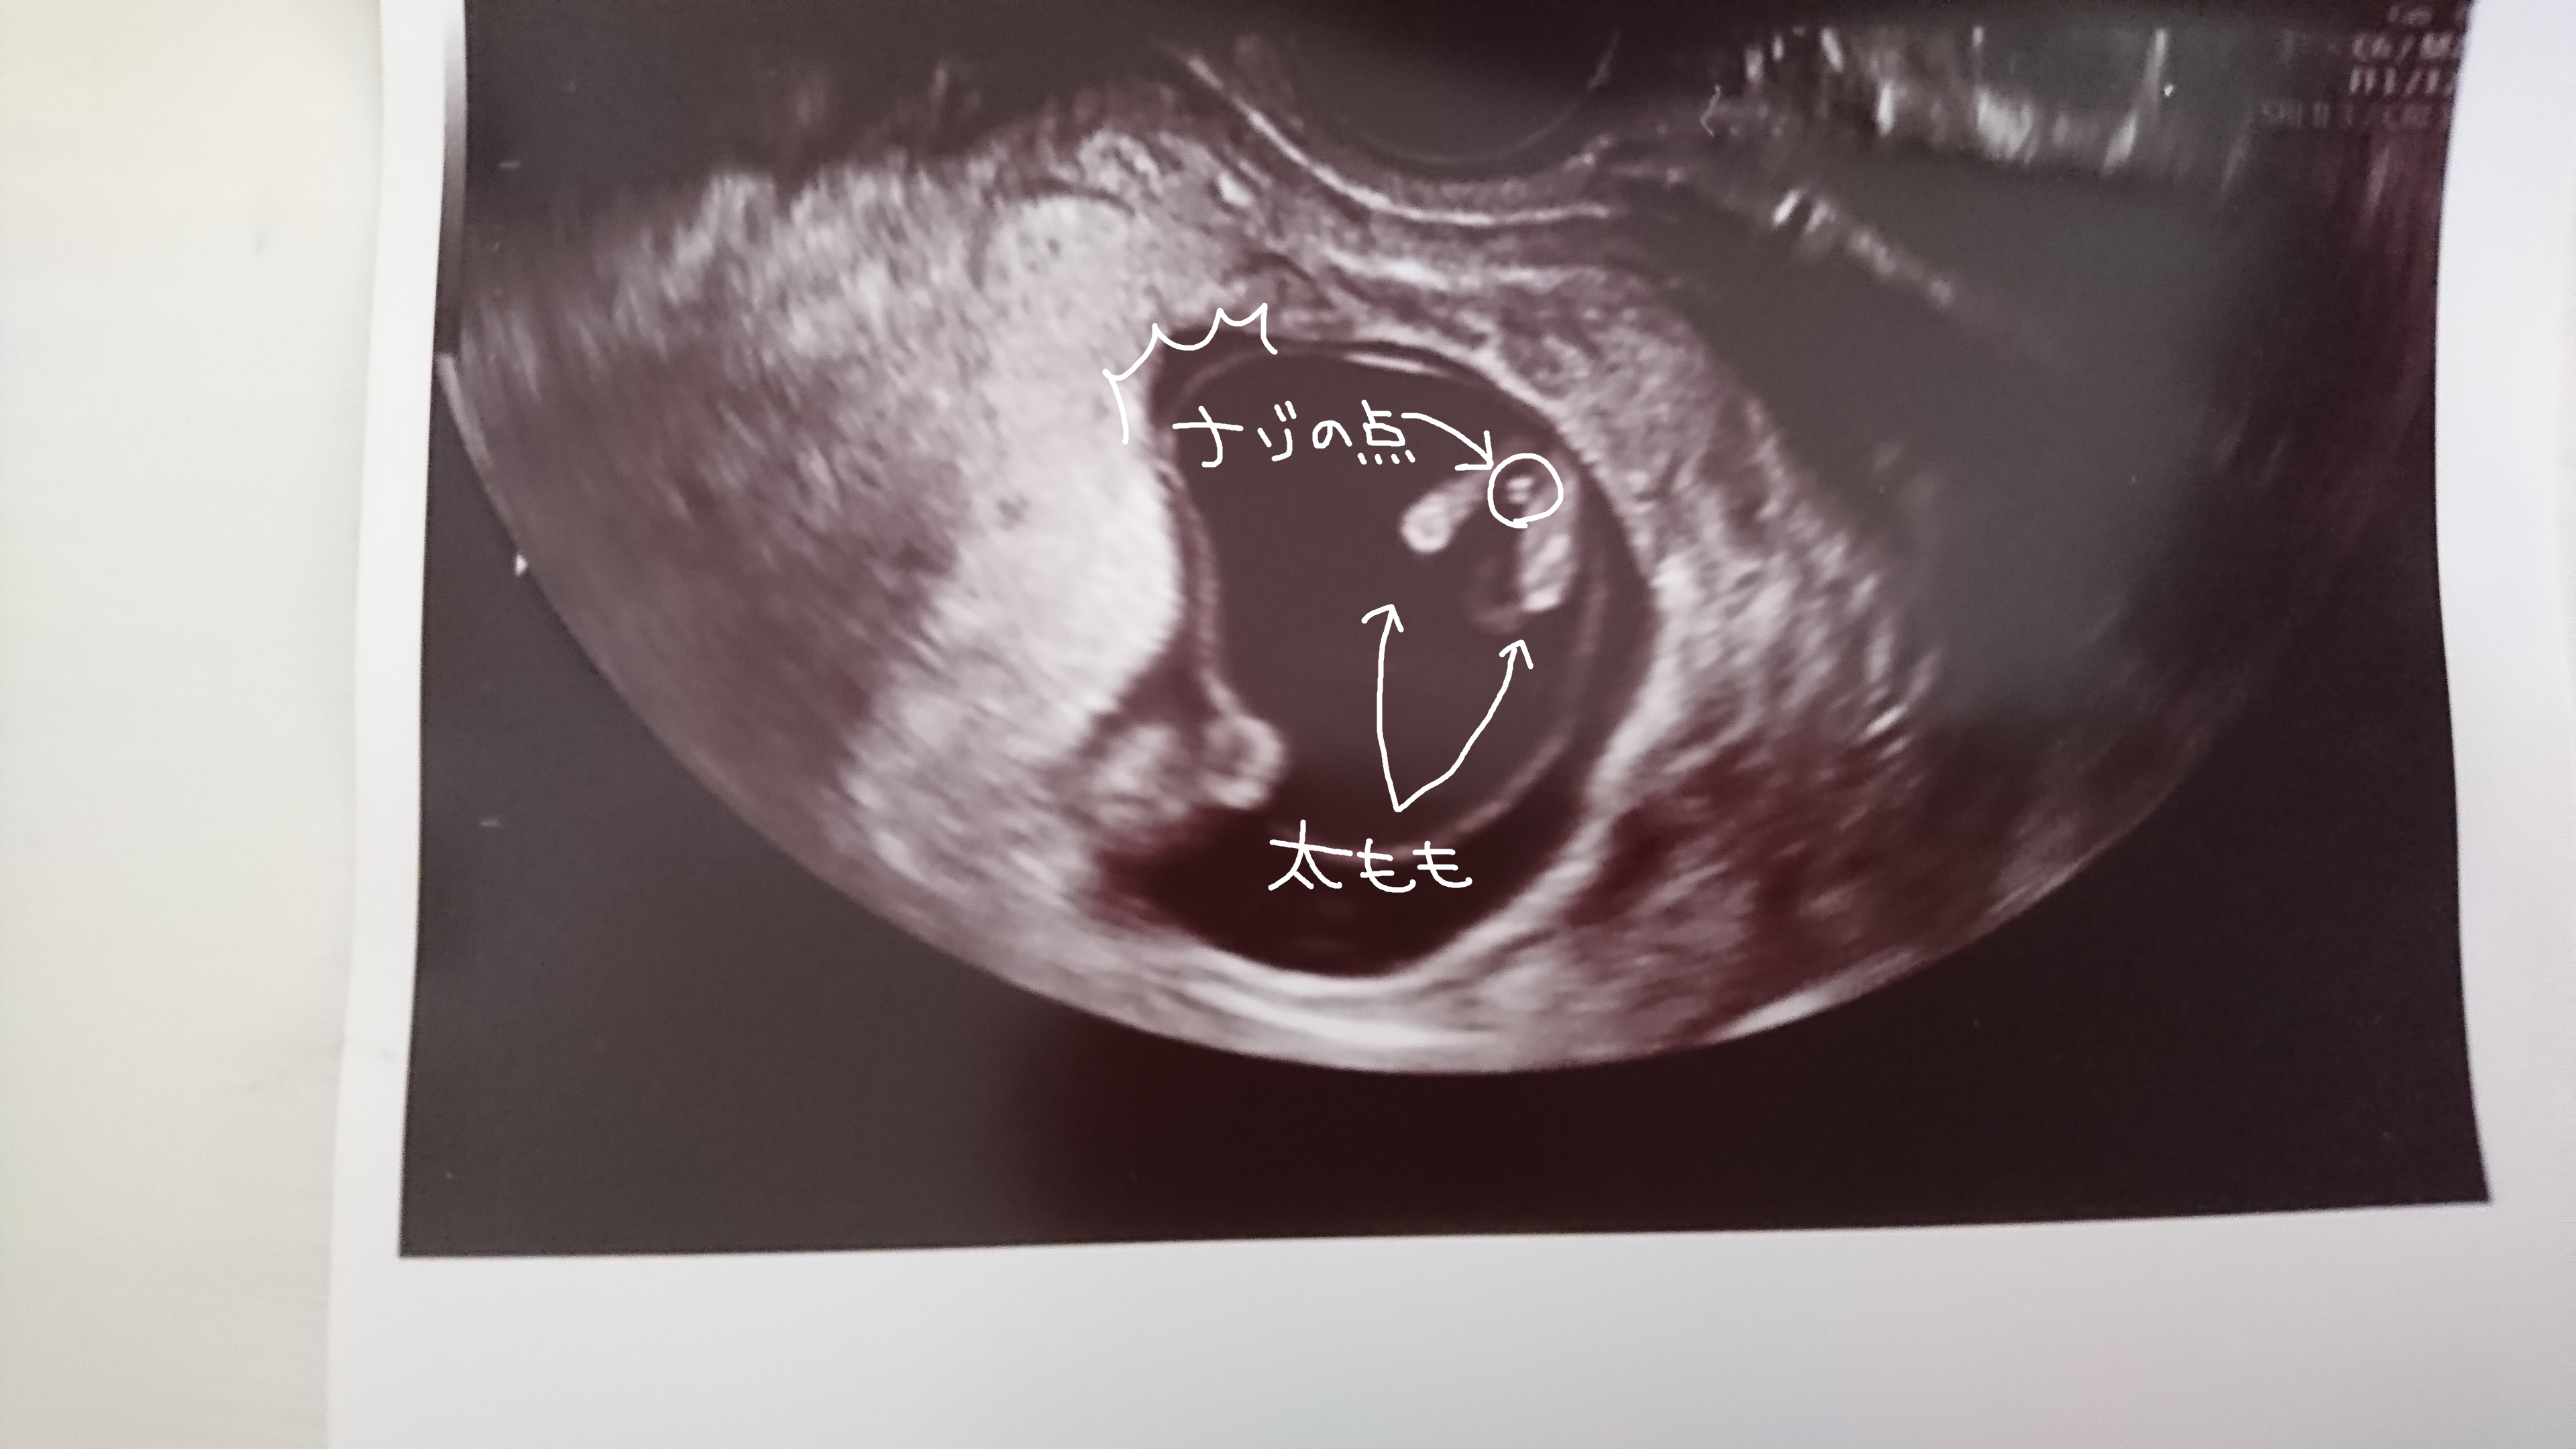

妊娠11 12 13週で性別が分かる Baby Nub ベビーナブ の見分け方を紹介

妊娠初期でも性別が分かる Baby Nub ベビーナブ ってなに 男児確定エコーあり わたしにとっては輝く日常

Babynub ベビーナブ 二人目に女の子を迎えたい

Baby Nub 12週で性別確定 エコー有 10 3人目妊娠中 By ぷてぃ Crooz Blog